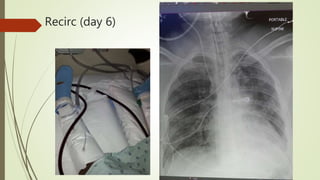

Recirc (day 6)

Decannulated (day 7)

Decannulated (day 7) APRV weaned to minimal so extubated on day 8  Bilateral Flail Segments  Reintubated and bedside trach next day  On APRV minimal settings for another week  Then HFNC via Trach  ATC and complete liberation from MC  Capped then Trach decanulated on floor